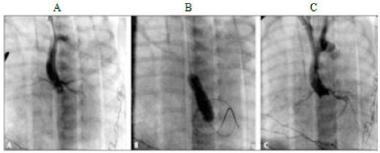

As imagens (A, B, C) abaixo demonstram o procedimento de radiologia intervencionista denominado aortografia em um recém-nascido com estenose aórtica crítica.

I. O balão posicionado ao nível da valva aórtica e a pequena incisura no balão durante a insuflação.

II. A ortografia pós-aortoplastia com aumento da área de abertura valvar e sem regurgitação aórtica.

III. Procedimento realizado através da artéria carótida direita. Posição ânteroposterior, demonstrando a mínima abertura da

valva aórtica (aspecto unicomissural).

Desta forma, correlacione as imagens abaixo com as etapas (I, II e III) e assinale a alternativa correta.